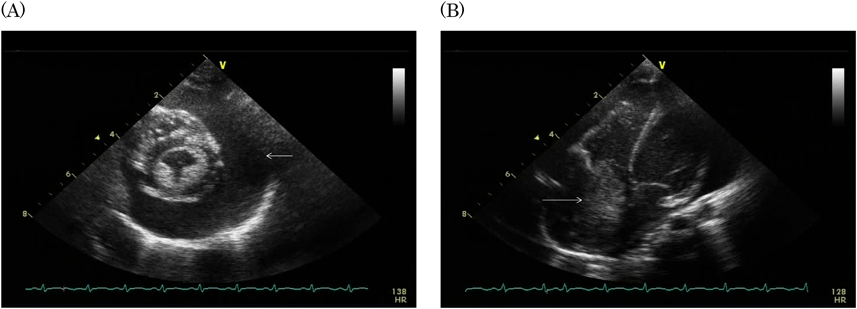

胸部エックス線撮影では心胸郭比67%と著明な心拡大を認めた.12誘導心電図は同調律,不完全右脚ブロックとIII誘導で異常Q波認めた.心エコー検査の傍胸骨短軸像と長軸像(Fig. 1)では,全周性に約15 mm心嚢水があり,左室拡張末期経(LVDd)=17.4 mm(z=-0.9)左室収縮率(LVFS)29%であった.四腔断面像では右房内に26×33 mmの内部不均一の腫瘤を認めた.腫瘤は右房壁に広範囲に接していて可動性はなく,右房内側の腫瘤表面は平滑であった.造影CTでは右房内に径27 mmの低吸収値の腫瘤を認めた(Fig. 2).血液検査では白血球数33,100/µL,CRP 10.3 mg/dL,血清アミロイドA 224 mg/mLと炎症反応の上昇を認め,IL-6 107.9 pg/mL,BNP 210.4 pg/mLと高値であった(Table 1).

Pediatric Cardiology and Cardiac Surgery 32(4): 314-318 (2016)

Fig. 2 Computed tomography showing a low-density space-occupying lesion in the right atrium of the heart and pericardiac effusion

(M=mass; RA=right atrium; RV=right ventricle; LV=left ventricle; PE=pericardiac effusion).